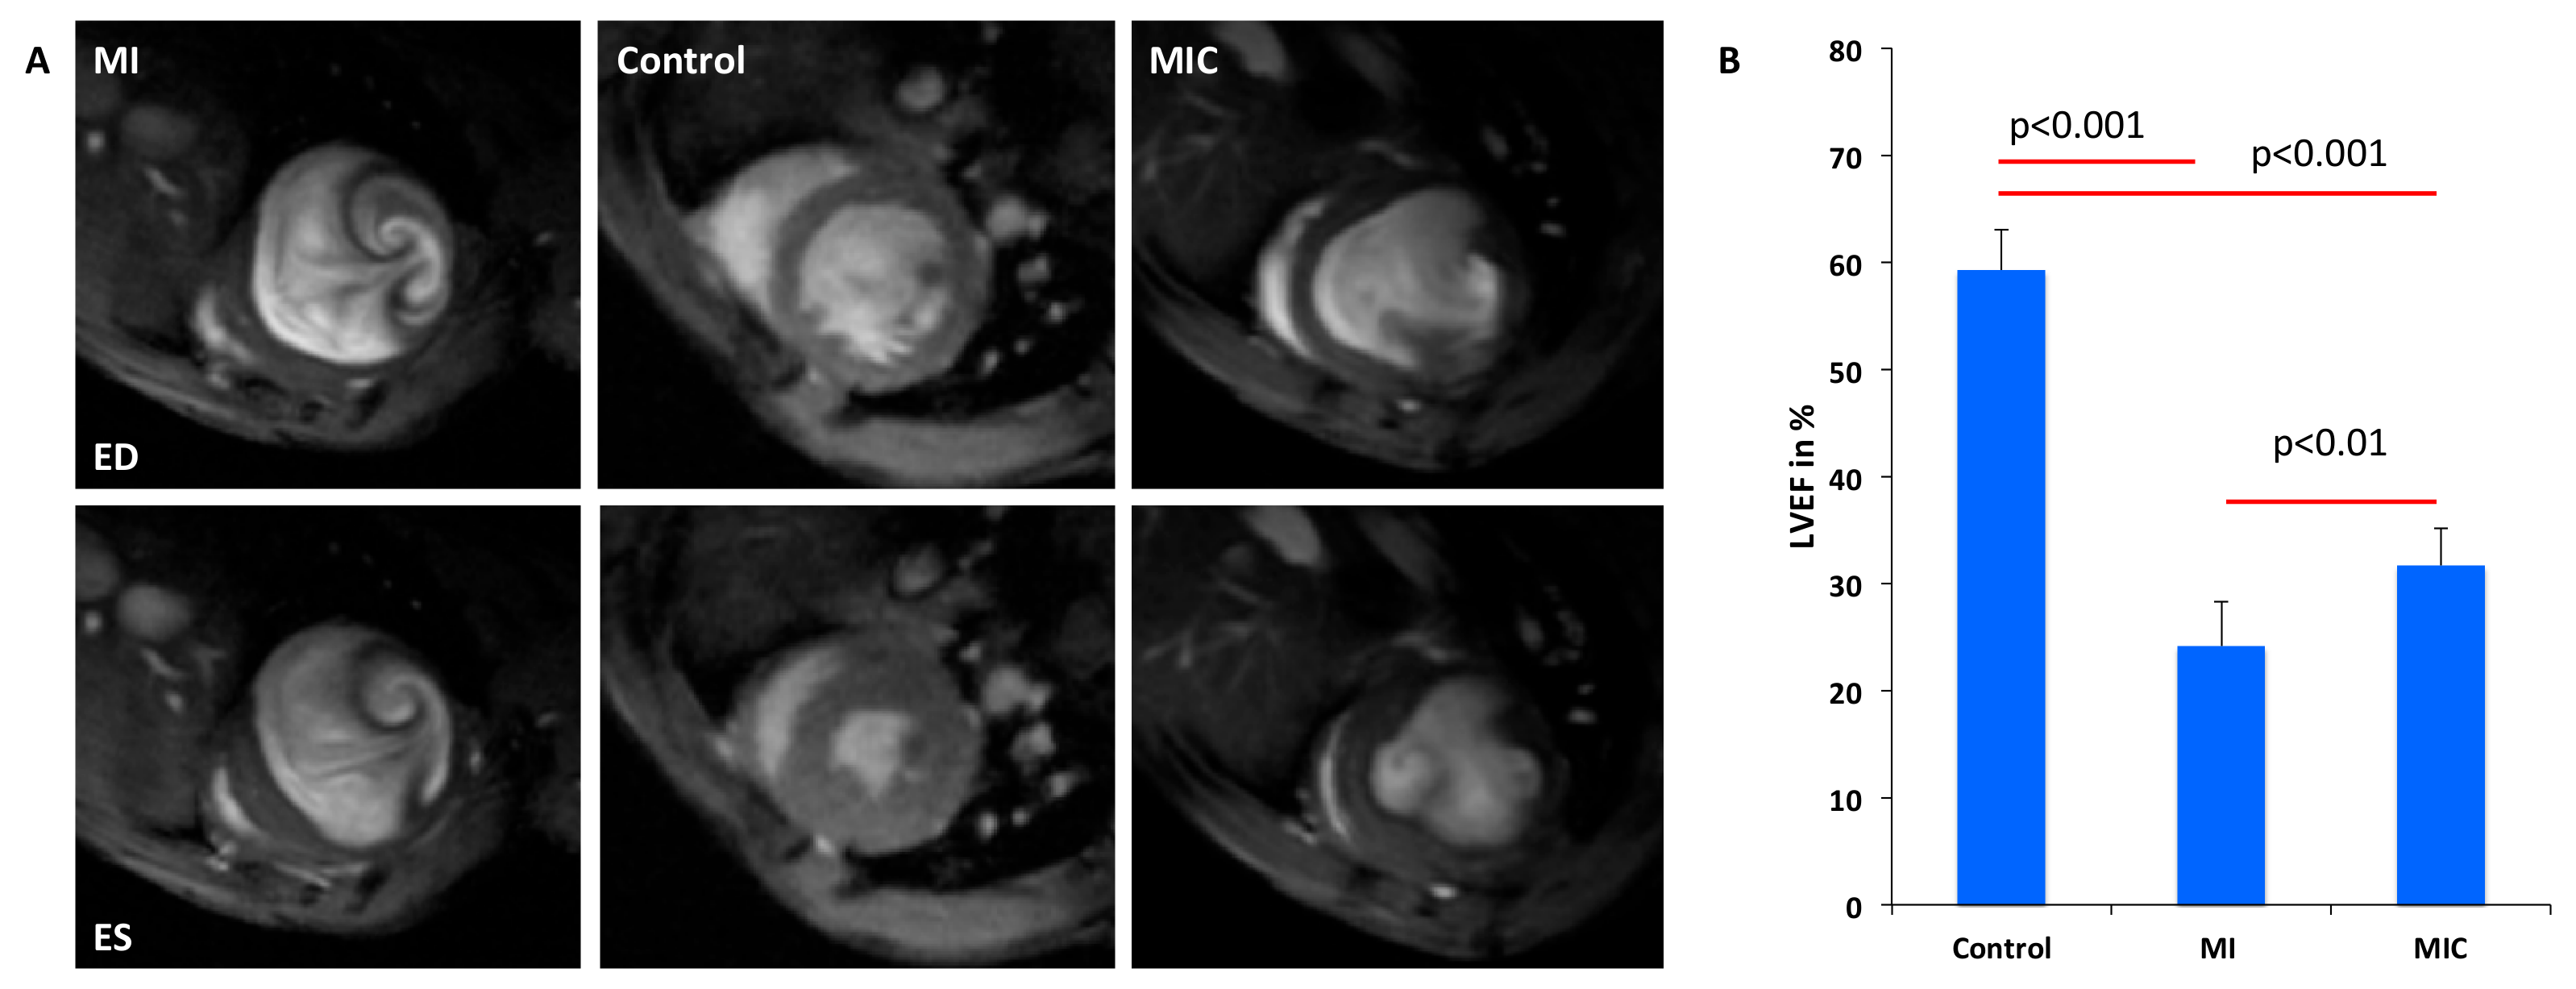

3.4. Improvement of Cardiac Function Through Cell Therapy Assessed by CMR